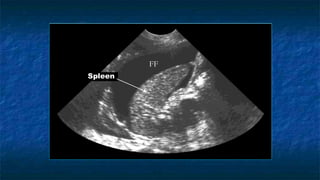

4)FAST: LUQ exam

 Evaluating

 Spleno-renal interface

 Possibility of fluid in splenorenal recess

and presplenic /subphrenic space( most

common space for fluid collection in

LUQ)

FF

Kidney

Spleen

Diaphragm